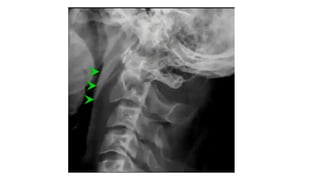

• #46 Soft tissue swelling Spinolaminar line c2 does not fall on the line Harris ring is a ring like structure resulting from proj of lat masses of c2 on its body. Ring disrupted Fat Body of c2 Thses could be the subtle radiolographic signs in hangman

Rule of Spence